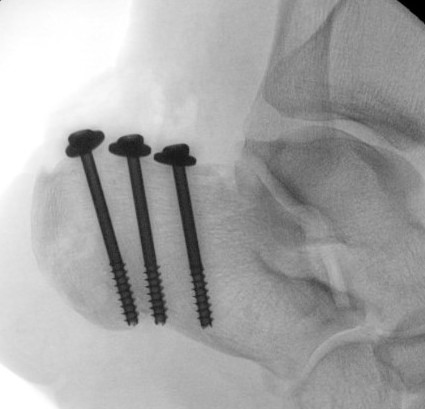

ORIF

Reduce fracture with clamps

Insert 2 - 3 screws

- bicortical fixation

- anterior to weight bearing posterior tuberosity

- cast with foot plantar flexed